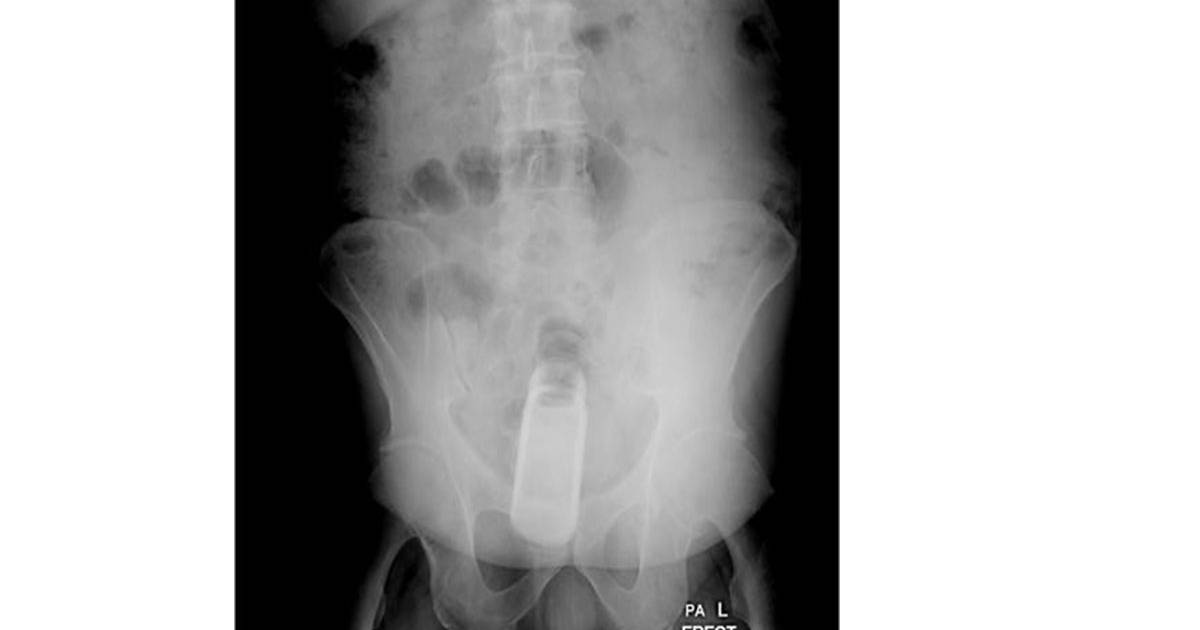

Los médicos interrogaron al paciente y luego le realizaron una radiografía que reveló que el hombre tenía un frasco en el recto, añadió.

Posteriormente, los médicos formaron un equipo de especialistas para extraerle en el quirófano el frasco que estaba dentro de un condón, precisó el portavoz del hospital.